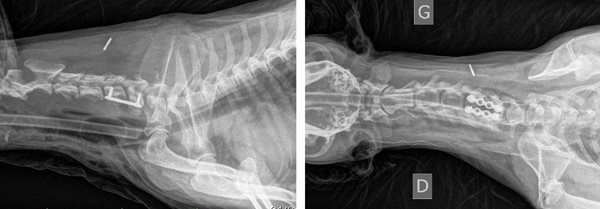

Myélographie Hernie Discale T12-T13

La myélographie est souvent suffisante pour établir un diagnostic et poser l'indication chirurgicale, cependant dans certains cas, en présence d'un gros oedème médullaire ou de difficultés de latéralisation, il peut être nécessaire d'avoir recours à des moyens d'imagerie tridimensionnels comme le scanner ou l'IRM.

Les imprécisions liées au caractère bidimensionnel de l'examen le rend actuellement obsolète face à la tomodensitométrie numérisée. Son usage peut encore se justifier en situation d'urgence neurologique chirurgicale et en l'absence de disponibilité d'un scanner. La myélographie, avec ses carences, demeure un examen utile, tant par sa simplicité de réalisation que par sa grande accessibilité matérielle (un simple appareil de radiologie permet d'y avoir recours).

Scanner d'une Hernie discale T13L1 extrusive chez un chien reformatages sagittal et coronale